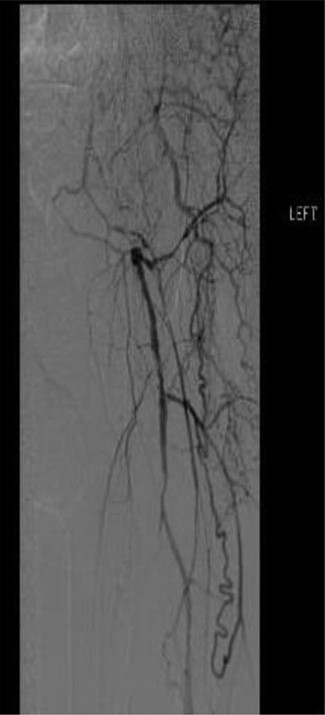

Workup began with noninvasive studies of the left lower extremity displaying aortoiliac occlusive disease and infrainguinal disease. Aortogram demonstrated a severely calcified aorta, patent left common iliac and proximal hypogastric arteries, with occlusion of the left external iliac, left common femoral and left superficial femoral arteries (Fig. 1). The right iliac system was patent apart from an occluded right hypogastric artery. A selective left lower extremity angiogram demonstrated reconstitution of the mid-to-distal profunda femoris artery (Fig. 2) to the proximal above-knee popliteal artery at the adductor hiatus (Fig. 3). Extensive collateralization was appreciated in the pelvis and lower extremity, between the residual left hypogastric artery and profunda femoris artery. Endovascular revascularization attempts were unsuccessful.

Selective left lower extremity angiogram demonstrating patent mid-to-distal profunda femoris artery and its collaterals